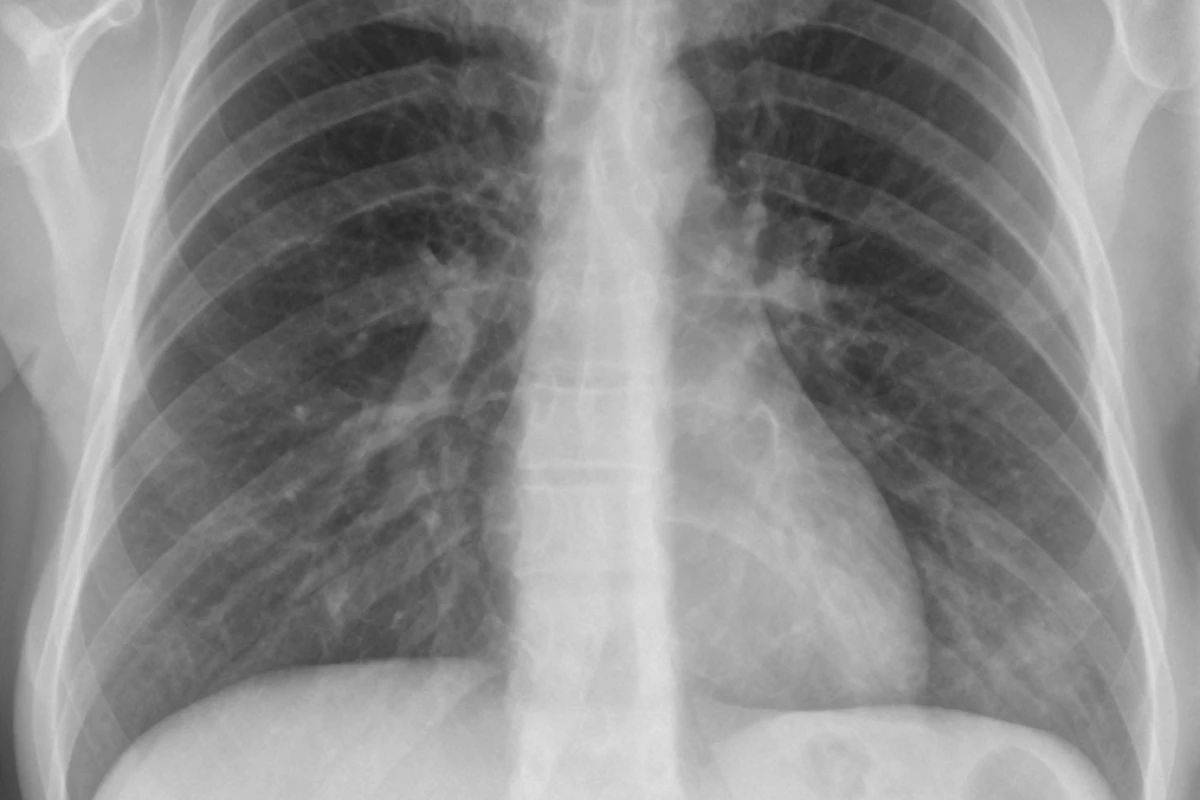

Diagnostic Procedures

Doctors use several ways to diagnose pneumonia. A chest X-ray shows lung inflammation. Blood tests help find the cause, like bacteria or viruses. Sometimes, a sputum test is done to check the mucus for infection.